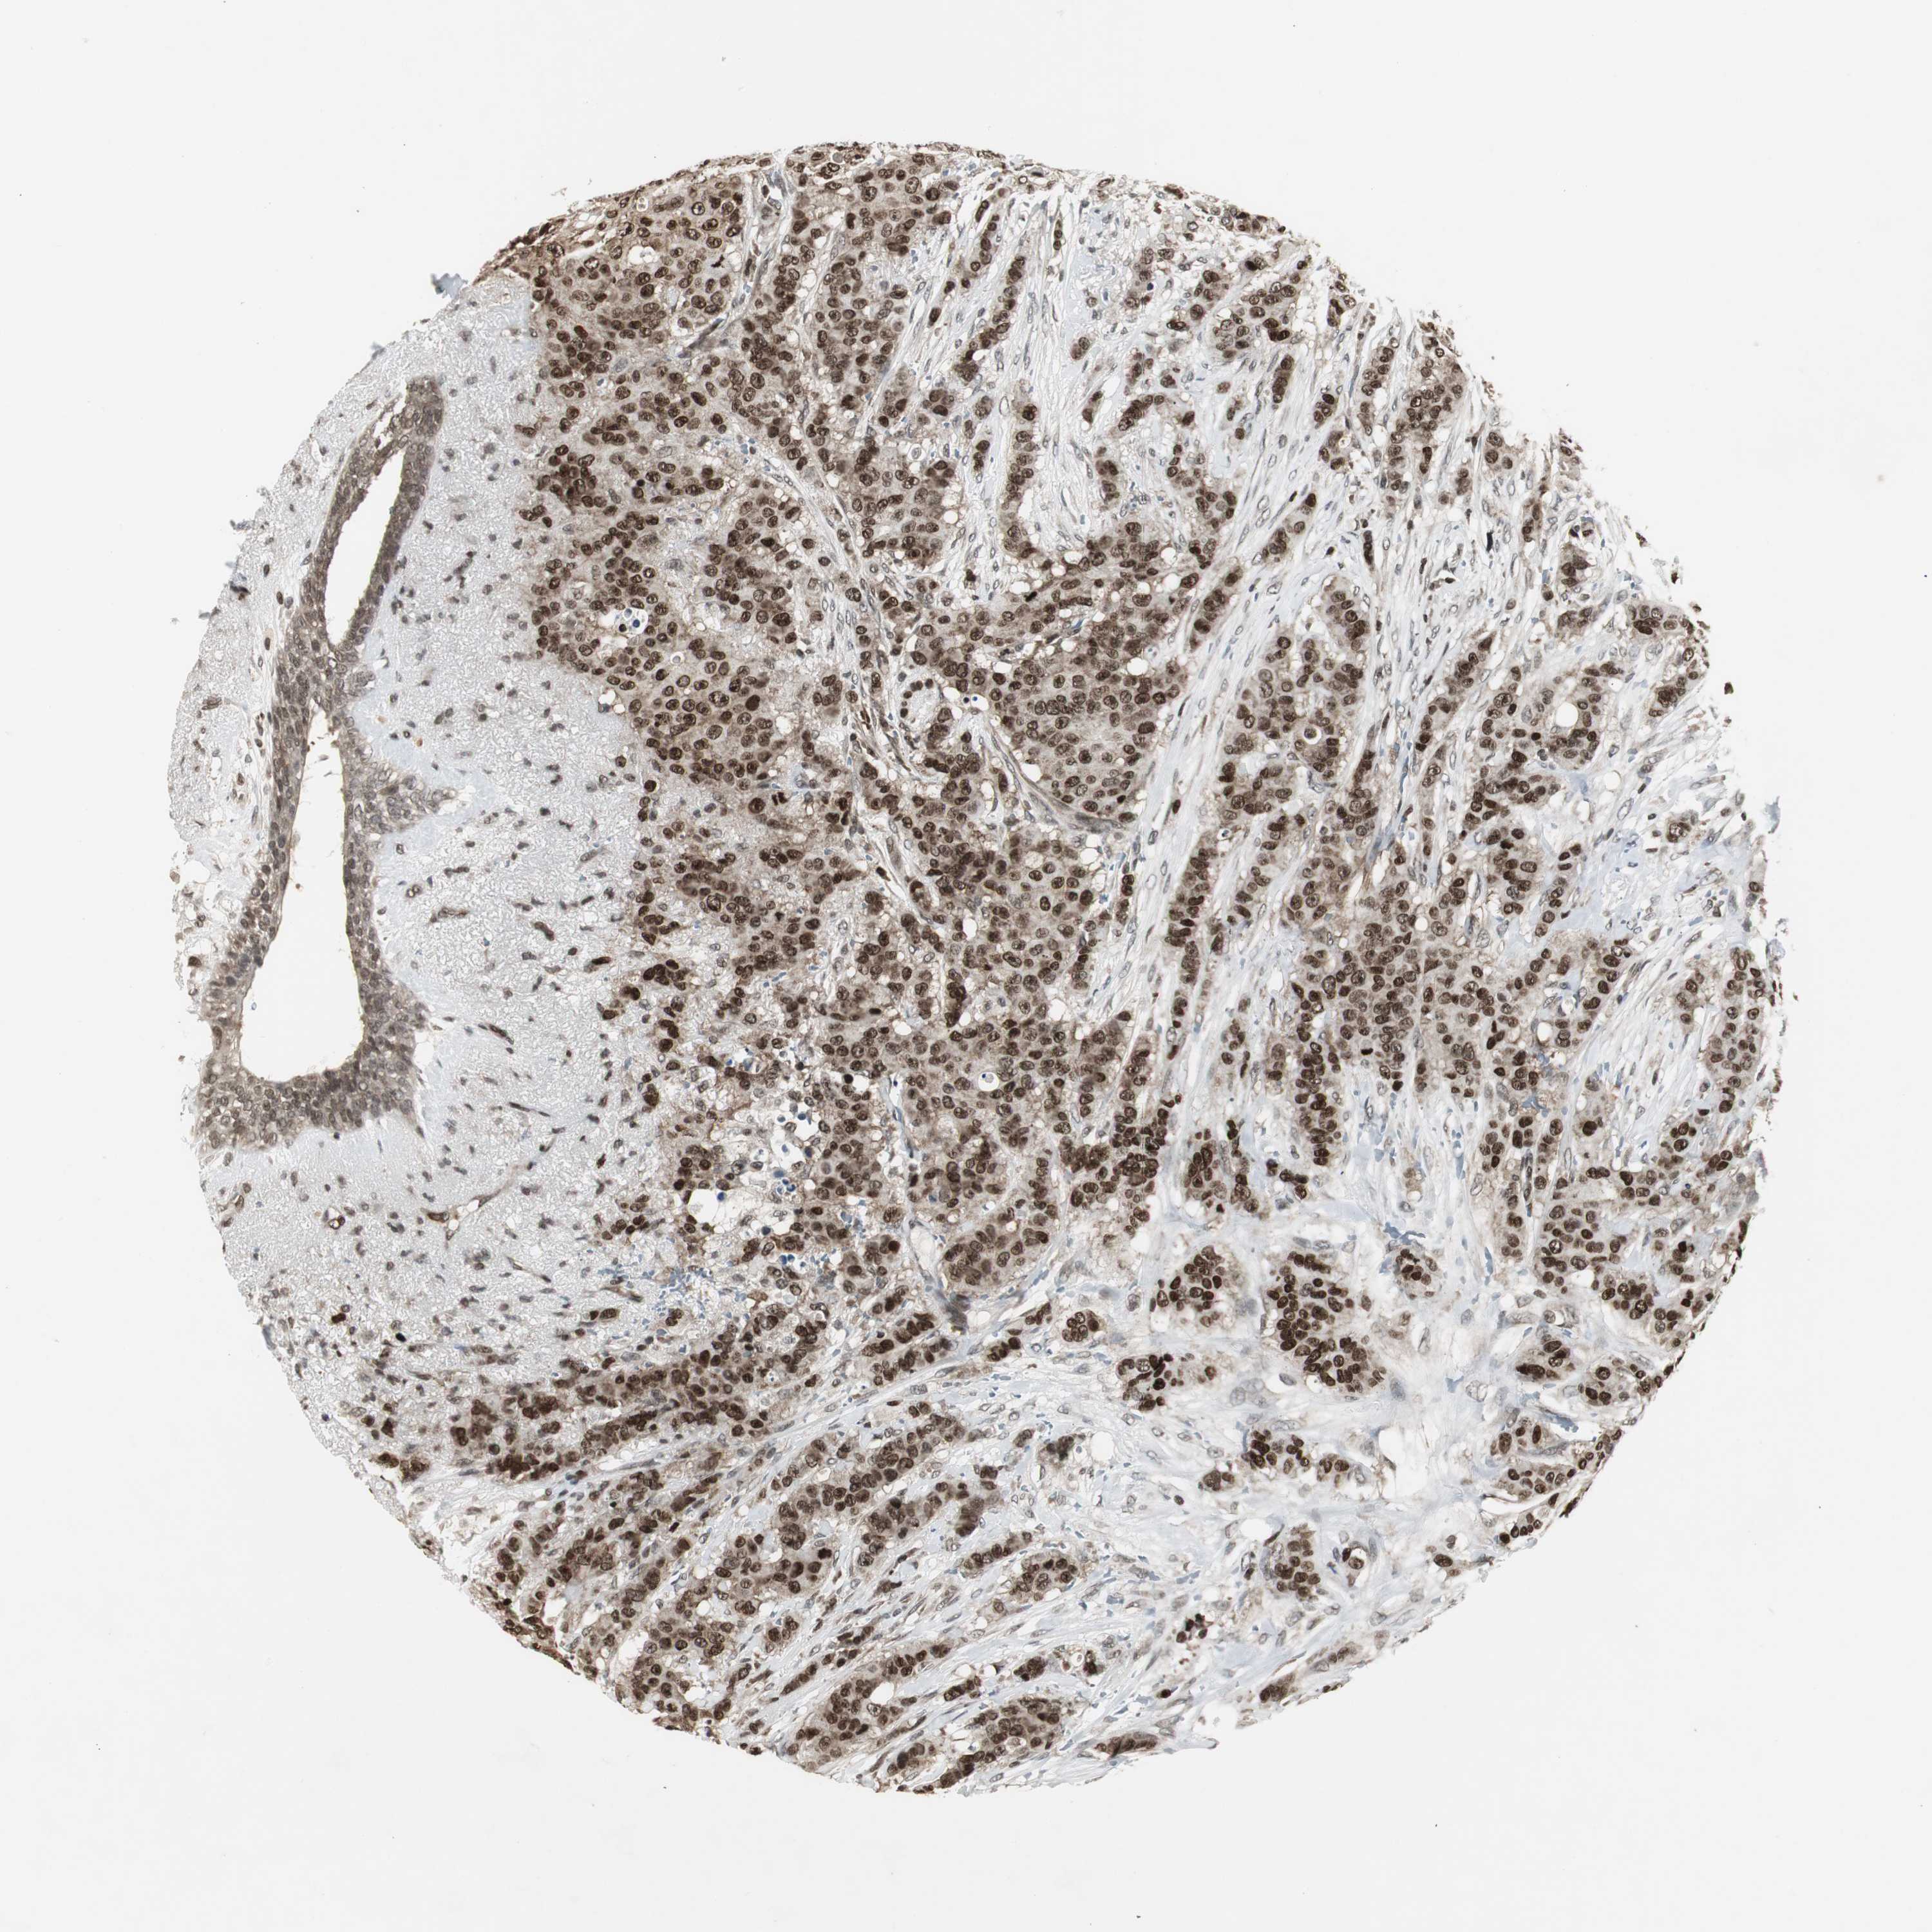

CANCER BREAST CANCER Show tissue menu

BRCA TCGA BRCA VALIDATION PROTEIN EXPRESSION

Breast cancer

Human cancer